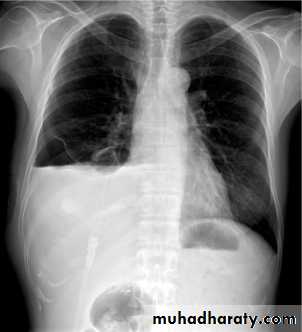

Lobular consolidation ( broncho pneumonia )

Very important to consider that pulmonary edema in normal sized heart have close similar appearance to broncho pneumonia

The important Golden Key differentiation is the cardiac size being enlarged in pulmonary edema .

Post primary TB broncho pneumoniacotton wool sign

Post primary TB Bronch pneumonia

Q ???? Be careful in description & DxBoth of them have similar appearance of broncho pneumonic shadow

36.lobuler consolidation (lobular pneumonia )37.discussion